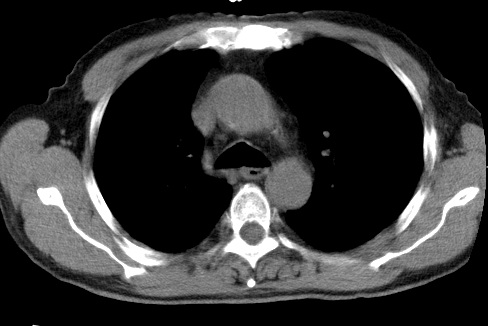

标题: CT24032:男65岁,咳嗽,吸烟20余年,无发热,咳痰 [打印本页]

标题: CT24032:男65岁,咳嗽,吸烟20余年,无发热,咳痰

考虑右肺中叶不张,请大家发表意见

右肺中叶不张、肺门轮廓增大,占位不除外;建议增强,必要时支气管镜详查。

右肺中叶支气管闭塞,中叶肺不张,右侧肺门见肿块影。中心型肺癌的可能大。建议支气管镜检查。

右中叶体积明显缩小,且其支气管未显示,先考虑:中心型肺癌班右中叶肺不张。

建议:支气管镜检查。

右肺门旁类圆形肿块影,右肺中叶不张,建议纤支镜检查。

1右肺门旁类圆形肿块影,右肺中叶不张,建议纤支镜检查

2右侧胸膜增厚,右侧叶间胸膜区钙化

3右肺下叶小囊状透亮影考虑肺气肿